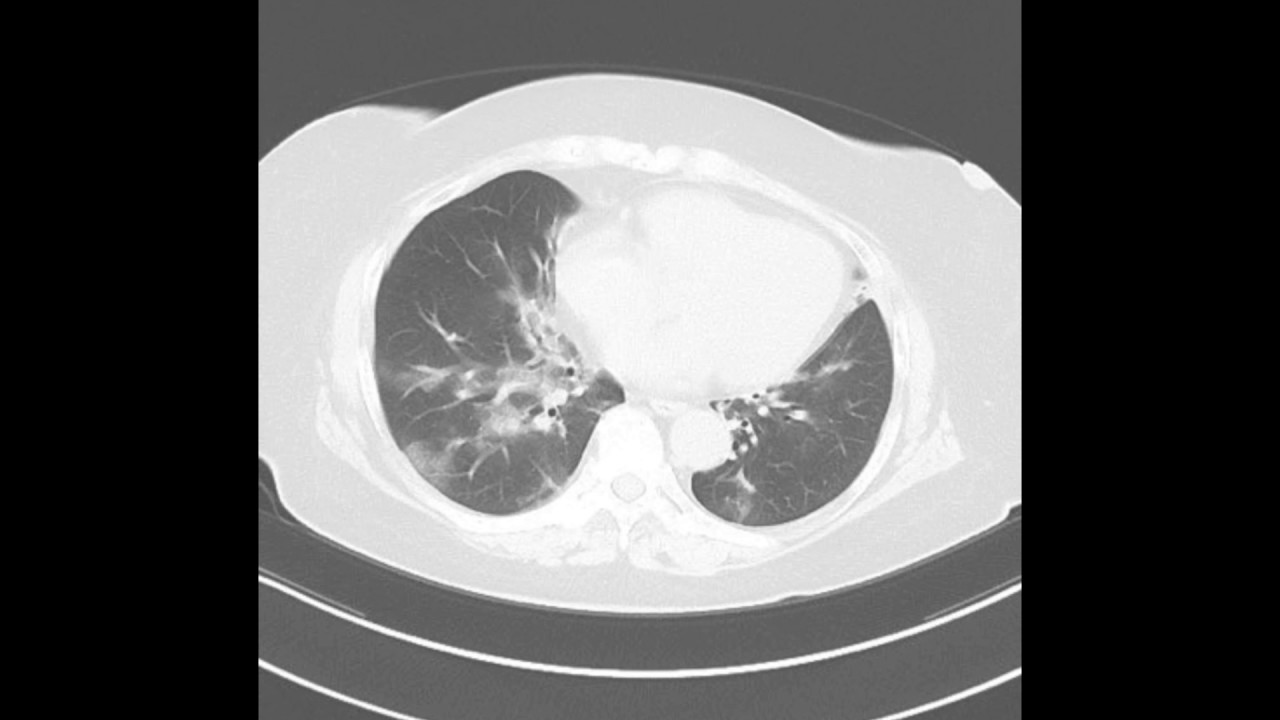

胸部単純X 線撮影では捉えられないCMV 間質性肺炎 の初期像を最も鋭敏に捉える9)(図2)推奨グレー ドB。 初感染例ではCMVAg が陽性化した時点,CMV disease 症状が発現(発熱)した時点で胸部CT を行うこ とが望ましい。初感染・既感染を問わず呼吸器症状が不全患者に発症した重症ニューモシスチス肺炎・サイト メガロウイルス肺炎にhfnc を使用することで,挿管人 工呼吸管理を回避出来た患者を報告している₁₀).上記の ように,加湿機能に優れ気道繊毛のクリアランス機能を見(血液培養からのクリプトコックスの検出,サイト メガロウイルス血中抗原検査における陽性細胞数の増 加)を基に判断すると,Cushing症候群による免疫不 全下での肺クリプトコックス症 クリプトコックス血 症とサイトメガロウイルス感染症を併発した